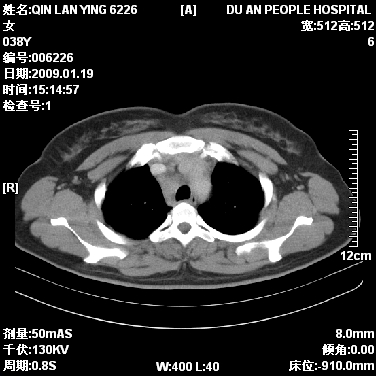

女,38岁,胸疼1个月。wbc:1万4

考虑----右肺中心型肺癌---阻塞性肺炎-----纵膈淋巴结及胸膜转移----肝脏转移

1)右肺中央型肺癌并右肺上叶阻塞性肺炎、节段性肺不张,纵隔淋巴结转移、右侧胸膜转移、肝脏转移。2)右侧胸腔少量积液。

1、右侧中央型肺癌并阻塞性肺不张,纵隔内、主动脉弓旁、右肺门淋巴结及肝脏转移可能性大,建议纤支镜进一步检查。

2、右侧胸腔积液。

本病例有几个容易诊断的地方:1、右肺上叶前段支气管闭塞,肺不张。2、淋巴结明显肿大。3、肝脏多个类圆形低密度影呈“牛眼征”改变,高度提示转移。

从影像学角度分析      右肺上叶中央型肺癌,并阻塞性不张、肺炎,纵隔淋巴结、膈顶淋巴结转移。

肝内两个大小不等低密度结节,内可见更低密度影,首先考虑肝内转移瘤,但联想到患者wbc1万4,建议楼主还是做个增强比较明确,除外肝脓肿的可能。